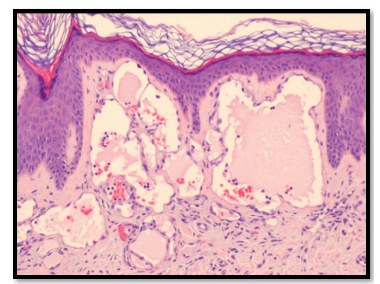

Figure 6:Histopathologic examination showing Lymphangioma Circumsciptum (Case 2).

An atypical aspect in the second case was the occurrence of Iron Deficiency Anemia (IDA), which is not typically linked with LC but may arise from chronic, low-grade blood loss due to vesicle rupture or ongoing oozing over time [15]. Although instances of IDA secondary to LC are uncommon, a comparable case was reported by Bittencourt et al. underscoring the necessity for clinicians to monitor hemoglobin levels in patients with bleeding-prone LC [16]. An unusual aspect in the second instance was the occurrence of Iron Deficiency Anemia (IDA), which is not typically linked with Lymphatic Malformation (LC) but may arise from chronic, lowgrade blood loss due to vesicle rupture or ongoing oozing overtime [17]. Although instances of IDA secondary to LC are infrequent, a comparable case was reported by Bittencourt et al. underscoring the necessity for clinicians to monitor hemoglobin levels in patients with bleeding-prone LC [18]. From a pathophysiological perspective, LC is regarded as a microcystic lymphatic malformation resulting from the sequestration of lymphatic tissue during embryonic development, leading to clusters of dilated lymphatic channels that connect with the superficial dermis [19]. Histologically, it is defined by thin walled, dilated lymphatic spaces lined by a single layer of endothelial cells, which may sometimes extend into the epidermis [8]. Although histopathological confirmation was not achieved in our cases due to the typical clinical features, it remains the diagnostic gold standard when the presentation is atypical.